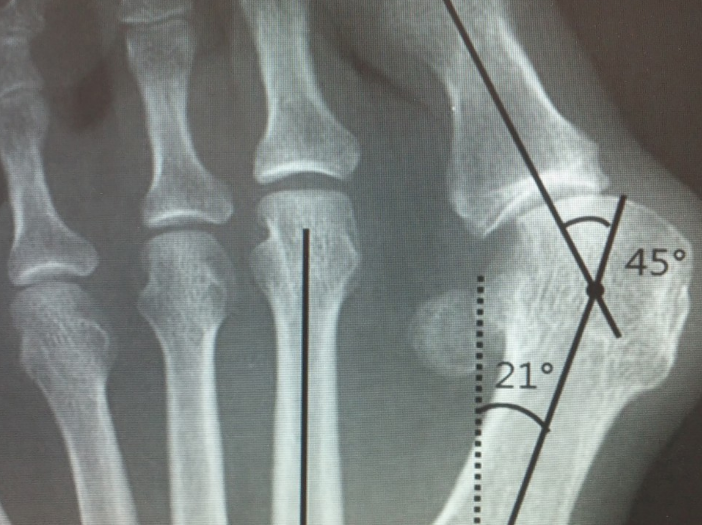

수술적 치료 방법은 증상과 정도에 따라 여러 가지 방법을 선택할 수 있습니다. 가장 대표적인 수술은 문제가 되는 엄지발가락 쪽의 제1중족골을 절골, 즉 부러뜨려서 이동시킨 뒤에 금속 나사 등으로 고정하는 방법입니다. 전통적으로 안쪽 피부 절개를 하여 수술을 시행했으나 최근에는 절개를 최소화 한 최소침습 무지외반 교정술 방법이 알려져 있어 환자들의 수술 후 회복이 매우 빨라졌습니다. 무지외반증으로 고생하고 있는 분들이 있다면 정확한 진단과 치료 방법에 대하여 정형외과 전문의와 상의하길 권장합니다